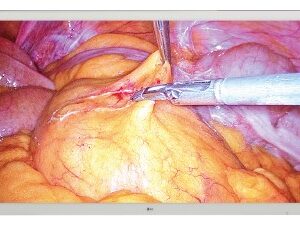

SKU: UP-27MD - Monitores LG, Monitores Médicos

Monitor Quirúrgico LG – 27HK510S

- Sector: Ideal para entornos de cirugía, endoscopia y laparoscopia.

- Excepcional calidad y precisión

- Resolución de 2MP (1920 x 1080) pixeles

- Calibración por hardware

- True Color Pro

- Diseñado para salas de operaciones

- Confort visual de larga duración

- Ancho: 654,4 mm.

- Alto: 412,90 mm.

- Fondo: 62,20 mm

- Peso: 7,70 Kg.

- Alimentación 100-240 VAC

- Seguridad: IEC60601-1 / IEC60601 -1 – 2